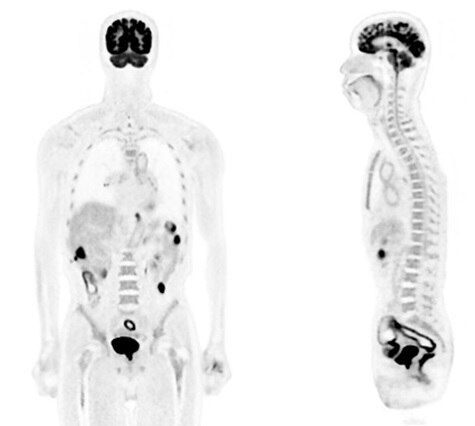

High resolution whole-body 18F-FDG scan demonstrating exceptional resolution in the spine and high image quality and lesion conspicuity in the right lung, enabling high diagnostic confidence in your PET/CT images.

Data acquired on an equivalent technology - SIGNA™ PET/MR.